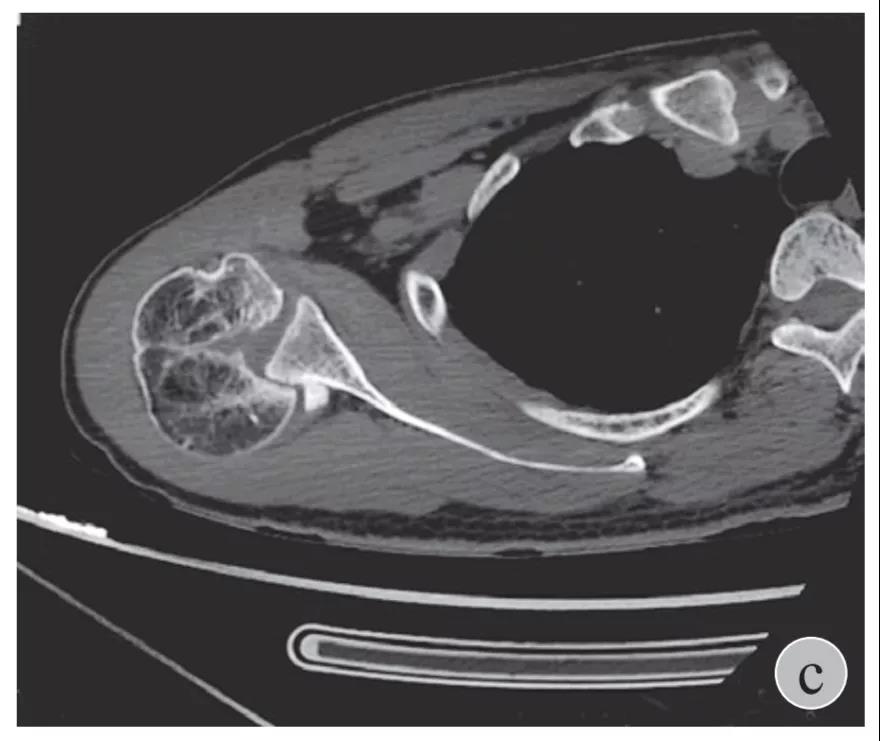

就诊我院后完善CT,诊断明确——左肩关节后脱位: